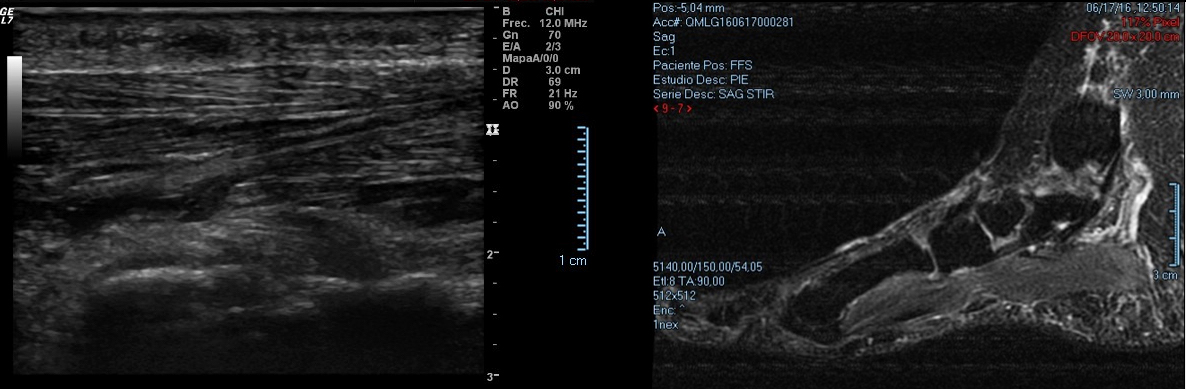

En general se pueden diagnosticar mediante la exploración clínica y una correcta anamnesis. A su vez nos apoyaremos en ecografías o RMN para visualizar la masa fusiforme, delimitar el grosor y diferenciar estructuras afectadas. A nivel de la zona dolorosa se puede apreciar una formación fusiforme de 15 mm hipoecogénica adyacente a la fascia plantar.

Los fibromas por si solos no causan dolor, es la presión directa sobre el fibroma la que puede dar lugar a dolor en arco plantar cuando caminamos, estamos de pie o en la práctica deportiva. Normalmente los síntomas se describen como sensación de cuerpo extraño en la planta del pie (como una piedra dentro del calzado) cuando traccionamos la fascia plantar.

El síntoma principal del fibroma plantar es la presencia de un bulto palpable en el arco del pie. En las primeras etapas, este nódulo puede ser pequeño y no causar molestias. Sin embargo, a medida que crece o si está ubicado en una zona de apoyo, puede generar dolor en el arco plantar y rigidez en la fascia plantar.